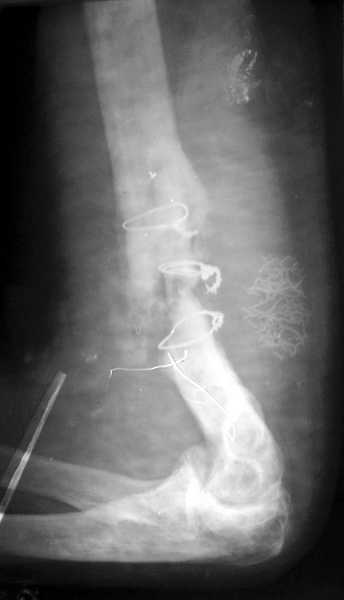

На примере два случая, извиняюсь за качество снимков, снимки и случаи из

Первая больная с "успехом" была прооперирована 6 раз различными методами

открытого и закрытого остеосинтеза, включая то, что в Кисловодске

заезжим австралийским "кудесником" на ложный сустав уложена скорлупа от

страусиновых яиц. Последняя операция одиноким локинг плейт в одной из

клиник.

Через год по поводу тех же проблем сделали ревизию, оригинальную

пластину оставили как есть, только укрепили добавлением еще одной

пластины и сделали костную пластику.

Через два месяца увидели признаки консолидации.

Второй случай, также после множественных операций:

пластина, аппарат, серкляж и парез нерва.

Также ревизия, из-за низкого состояния доступ был сделан через

остеотомию локтевого отростка.

Ложный сустав фиксирован двумя локинг плейт с аутокостной пластикой,

также через два месяца увидели признаки консолидации.

Движение в суставе разрешили в две недели.